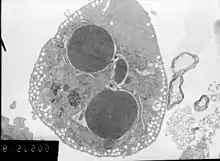

В просвечивающем электронном микроскопе (ПЭМ) для формирования изображения используется высокоэнергетический электронный пучок. Электронный пучок создается посредством катода (вольфрамового, LaB6, Шоттки или холодной полевой эмиссии). Полученный электронный пучок ускоряется обычно до 80—200 кэВ (используются различные напряжения от 20 кВ до 1 МВ), фокусируется системой магнитных линз (иногда электростатических линз), проходит через образец так, что часть электронов рассеивается на образце, а часть — нет. Таким образом, прошедший через образец электронный пучок несет информацию о структуре образца. Далее пучок проходит через систему увеличивающих линз и формирует изображение на люминесцентном экране (как правило, из сульфида цинка), фотопластинке или ПЗС-камере.

Основными недостатками ПЭМ являются необходимость в очень тонком образце (порядка 100 нм) и неустойчивость (разложение) образцов под пучком.